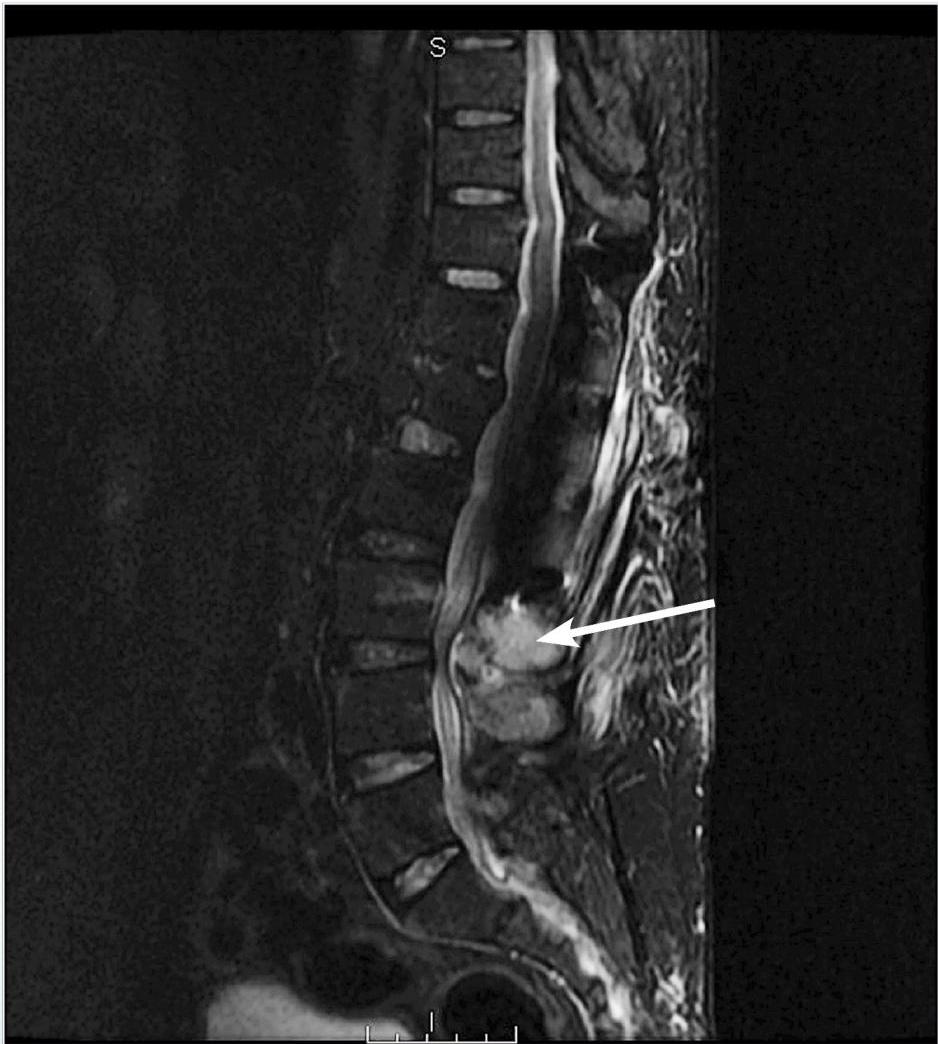

Figure 3. Osteomyelitis And Abscess

Magnetic resonance imaging reveals edema of paraspinal muscles and a fluid collection near L3-L4 with possible osteomyelitis (see arrow). The patient underwent interventional radiology abscess drainage that grew methicillin-sensitive Staphylococcus aureus. He was treated with 6 weeks of intravenous nafcillin.

Image courtesy of Pierre Borczuk, MD.